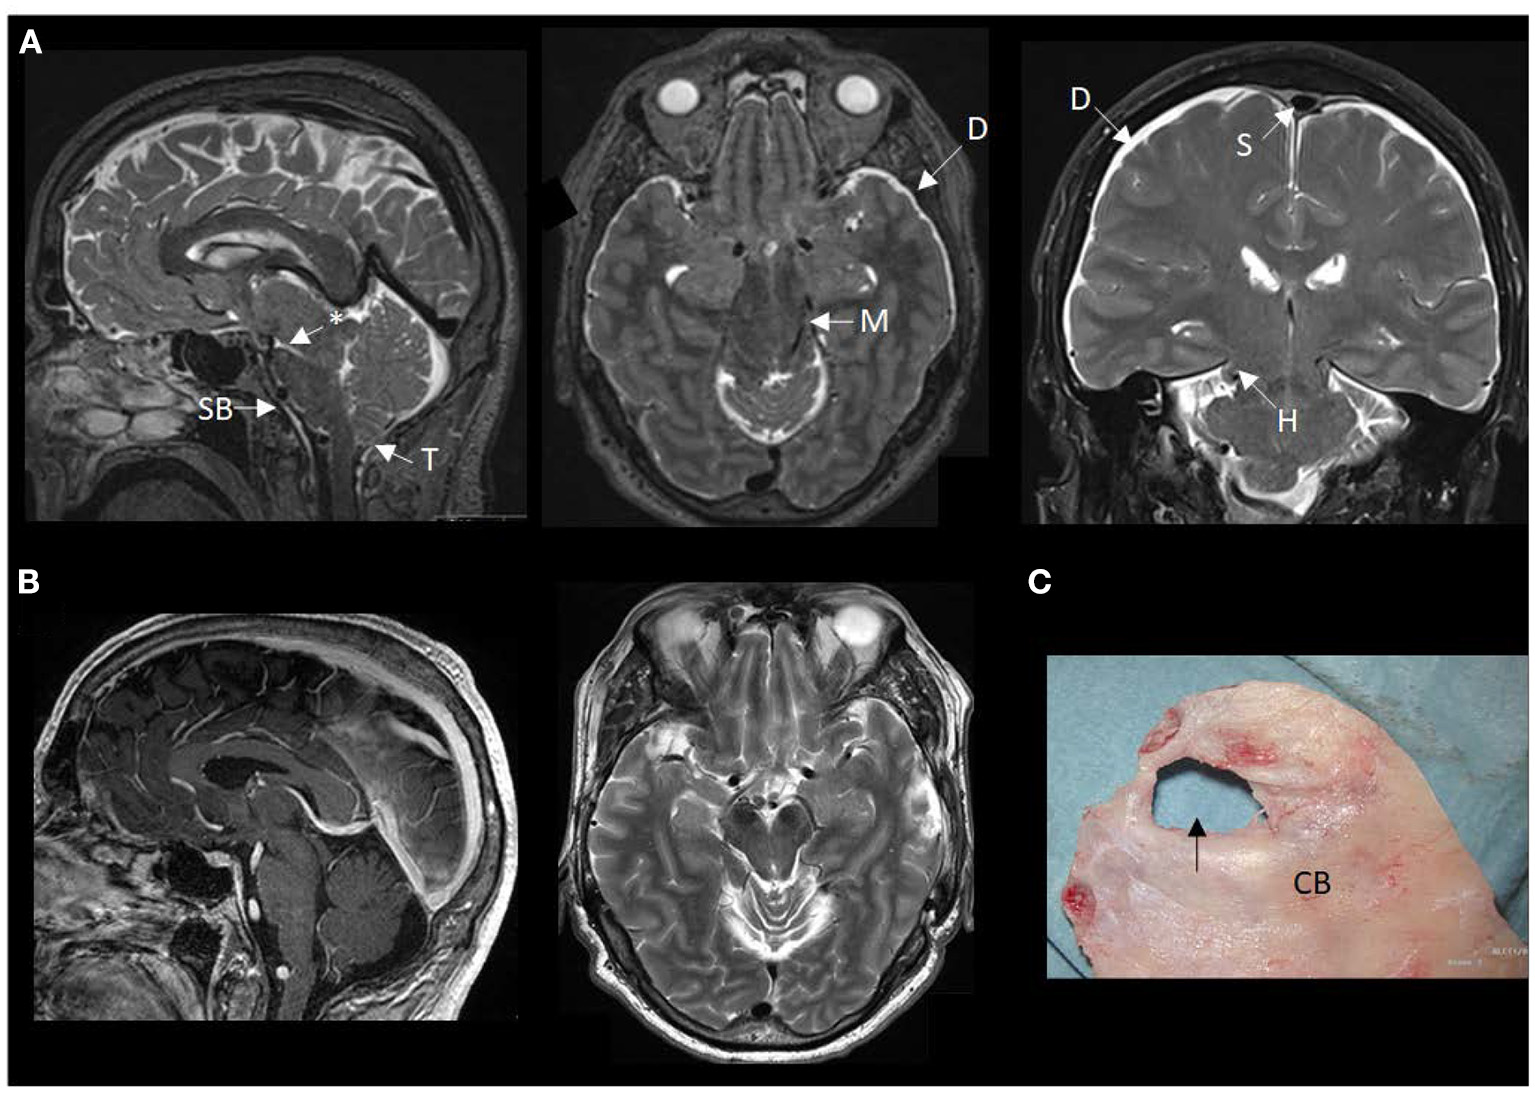

During his stay in our department, imaging showed severe brain sagging with subsequent CSF flow obstruction through the cerebral aqueduct (Figure 2). A comprehensive search for CSF leakage was performed; dynamic computed tomography (CT) myelogram and repeated craniospinal MRI after administration of intrathecal gadobutrol (Gadovist, Bayer, GE), according to our department's protocol (5). However, no CSF leak was identified. Continuous intracranial pressure (ICP) monitoring revealed severe intracranial hypotension with ICP scores < − 10 mmHg (Figure 3). The mean wave amplitude (MWA) was within the normal range, suggesting no impaired intracranial compliance (6). The patient deteriorated further and developed severe antegrade amnesia, stereotyped and bizarre behavior, becoming socially and sexually inappropriate. At one point, he assaulted the nurse in his room, thus acquiring surveillance by a security guard. He lost insight, and his decision-making became seriously hampered. For instance, he insisted to divorce his wife. Mini-Mental exam score worsened in a matter of weeks from 26/30 to eventually a point where he could not cooperate for the test.

Figure 2

MRI findings of brain sagging dementia in this case. (A) The preoperative MRI in sagittal, axial and coronal planes show typical signs of intracranial hypotension, including sagging brainstem (SB) toward the clival bone, downward tonsillar (T) ectopy, smaller ponto-mesencephalic angle (indicated by an asterisk), enhancement of the dura (D), rounding of the cross-section of the dural venous sinus (S) indicative of dural venous engorgement, transtentorial herniation (H), and reduced space for the mesencephalon (M). (B) The postoperative MRI in sagittal and axial planes demonstrate reversal of the MRI signs of brain sagging. (C) The cranial bone (CB) with a defect (indicated by an arrow), as presented during surgical exploration.

Due to his rapid clinical decline, a two-step cranial surgical approach was suggested, and his family consented. A cranial defect corresponding to his childhood head trauma was evident during the surgical exploration (Figure 2). The CSF leakage site was repaired, and an external ventricular drain was placed to overcome the supratentorial hydrocephalus induced by the brain sagging and subsequent CSF outflow obstruction. The splitting of the tentorium on the left side was also performed. The right tentorium was split in the second surgical step, and herniated brain tissue was resected. Despite a transient post-operative clinical improvement, his condition deteriorated. He became drowsy and showed clinical signs of herniation upon attempting to withdraw the drain. Therefore, he received a ventriculoperitoneal shunt with Codman-Hakim vale on a low setting (5 cmH2O).